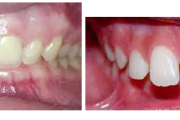

Ravijärgne seis. Jäävhammas on täielikult lõikunud.

) Röntgenülesvõte. Ülemise esimese jäävmolaari lõikumine on takistatud 2. piimamolaari tõttu

Esimese jäävmolaari ektoopiline lõikumine